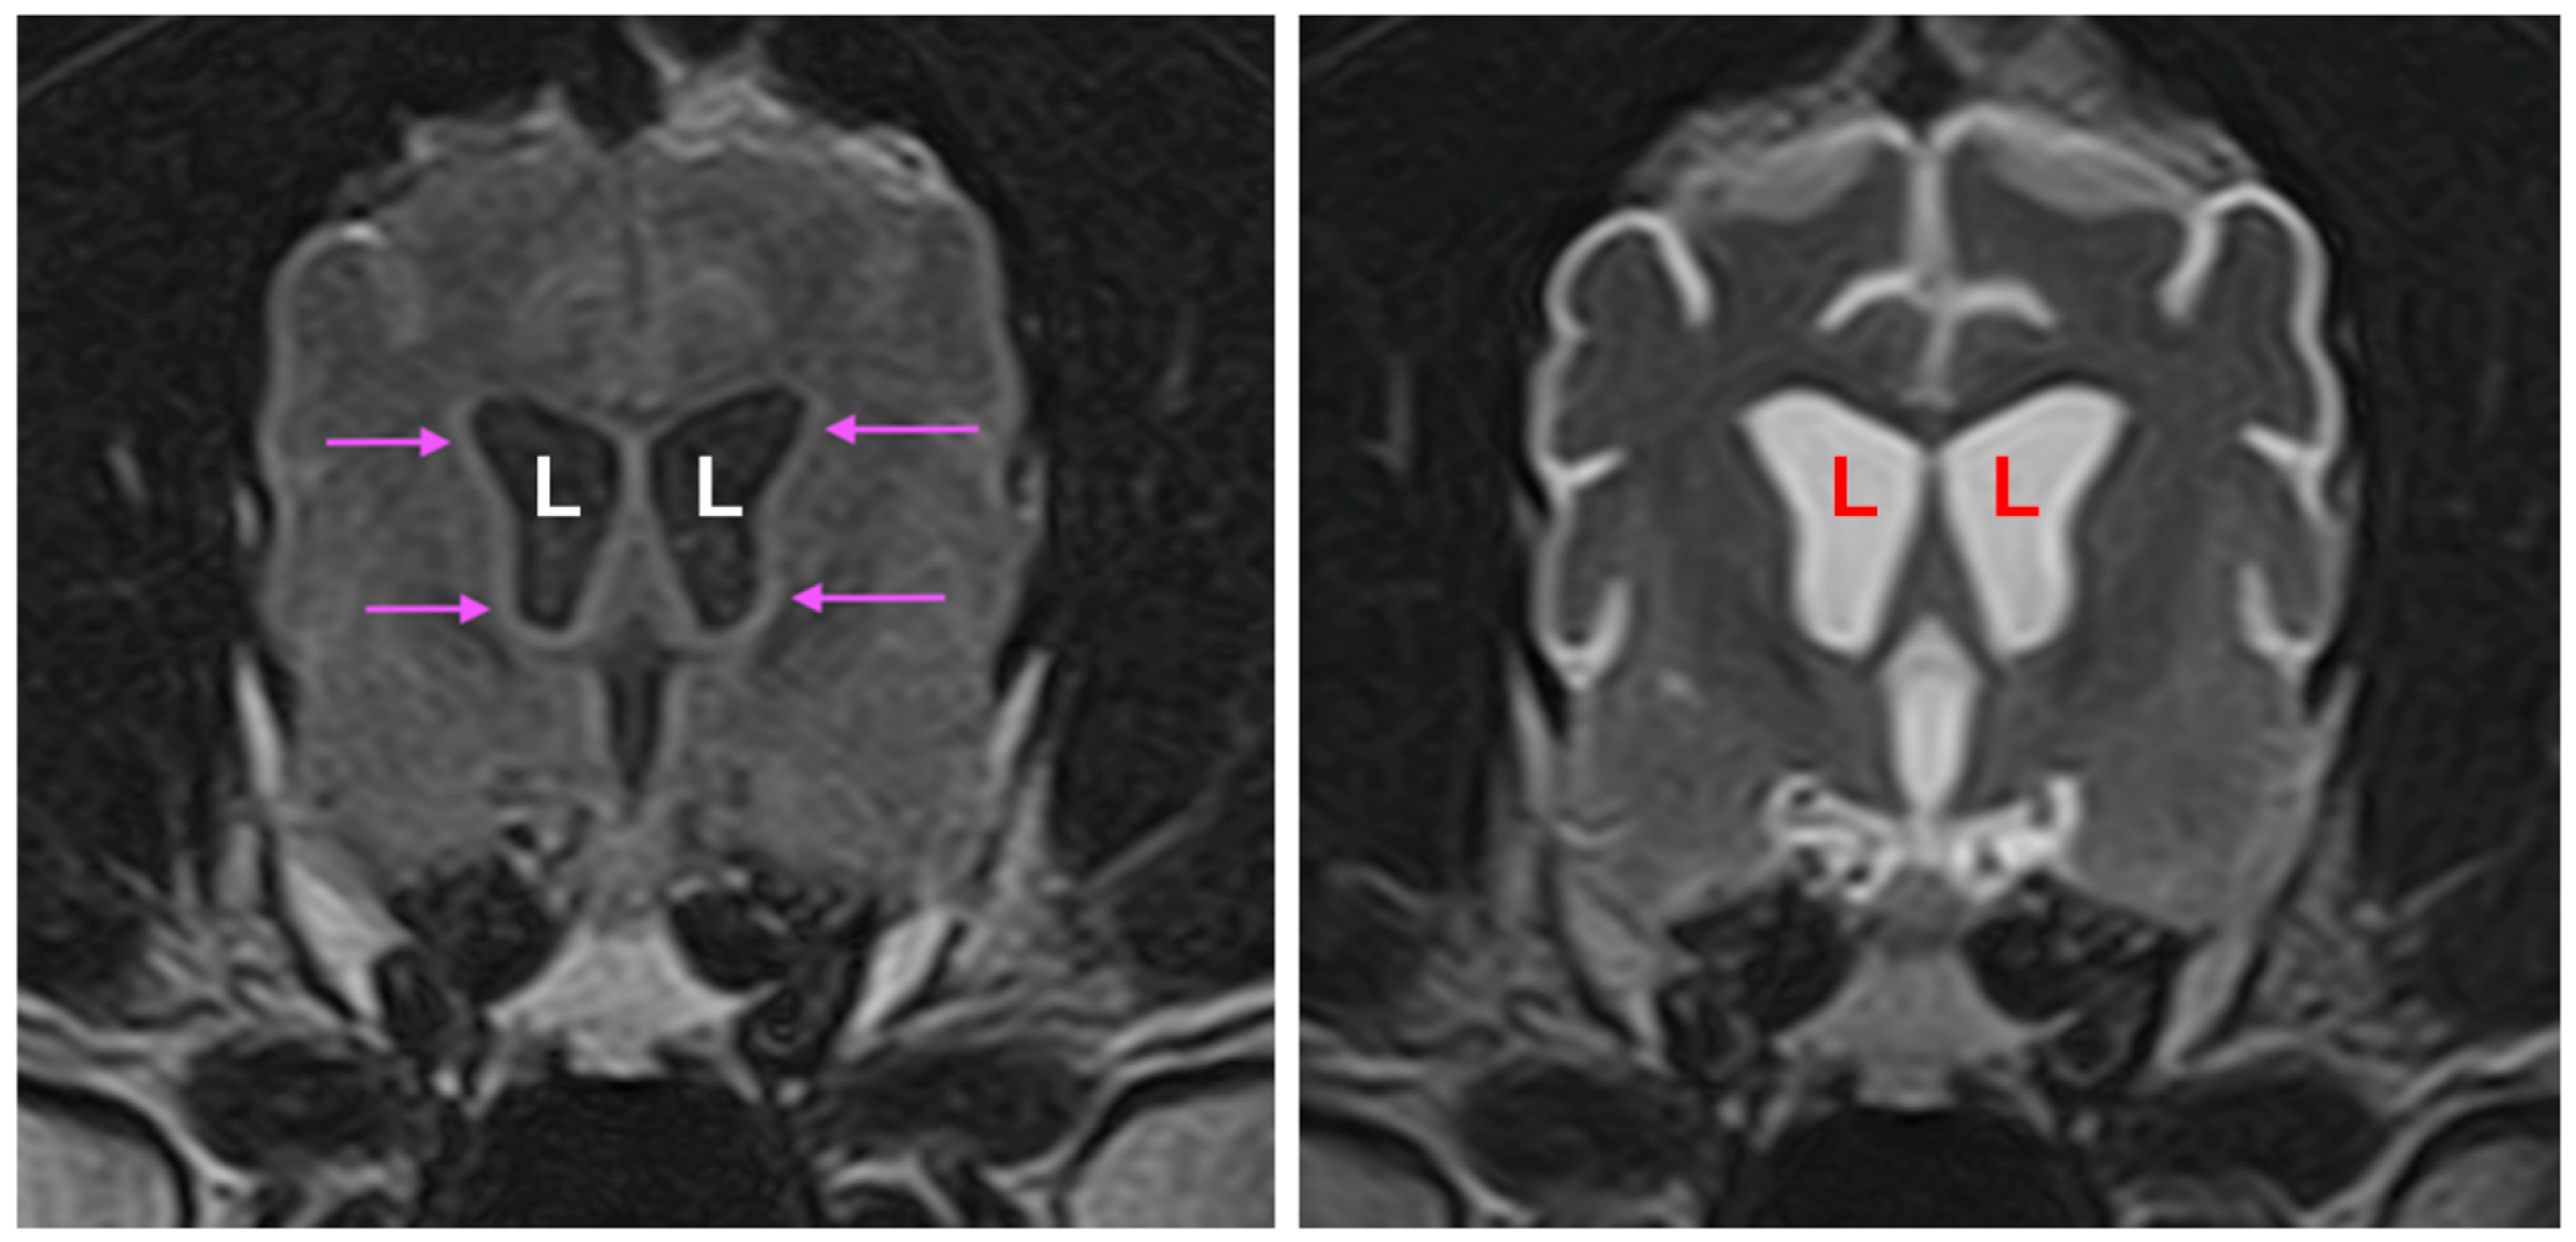

3.1. Disease Phenotype